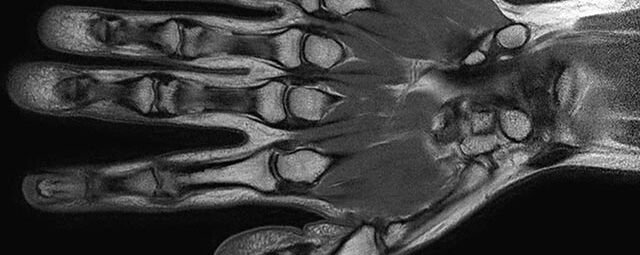

Gelenke

• Beurteilung von Knochen, Bändern und anderen Weichteilstrukturen der Gelenke nach Unfall.

• Arthrosediagnostik (Knorpelschaden)

• Impingement-Symptomatik

• Ursachenklärung bei wiederholter spontaner Gelenkluxation

• Ausbreitungsdiagnostik bei Gelenkentzündung, z.B. im Rahmen von rheumatischen Grunderkrankungen